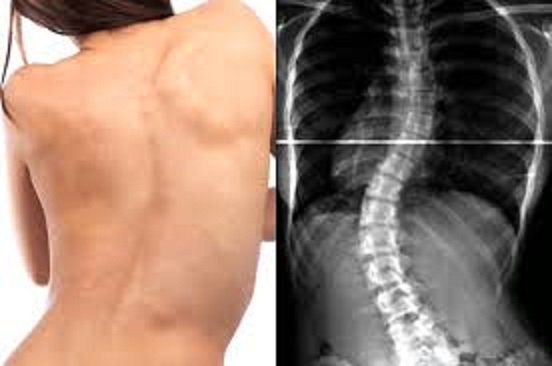

Se ve bien el diseño de la botella, pero así inclinada parece que tiene escoliosispic.twitter.com/pjPFDM0nxg